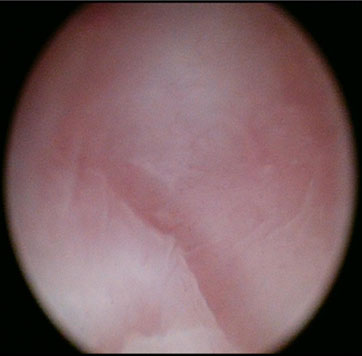

The patient was consented for examination under anesthesia (EUA), hysteroscopy, and dilation and curettage of both hemiuteri if possible. At EUA and vaginoscopy, the vagina was a blind ending pouch of about 5–6 cm in length, and the cervix was absent. The vaginal vault was smooth with no dimpling or firmness to suggest the presence of an underlying cervix (Figure 1). In the absence of communication between the vaginal vault and the uterine body, neither hysteroscopic assessment of either uterine cavity nor endometrial sampling could be undertaken.

Figure 1: Vaginal vault with no cervix visible.